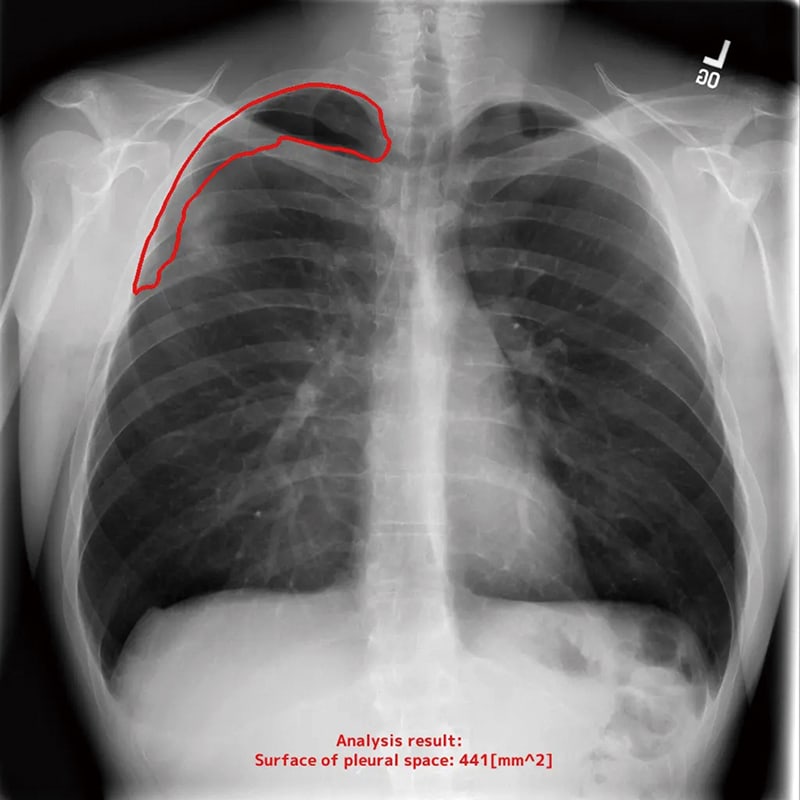

Identify and measure the area of air contents in the chest cavity

On a clinical site, detecting lung atrophy is conducted and measured by a manpower, which occurs human errors.

This automated measurement software is designed to improve an accuracy in comparing with previous images.